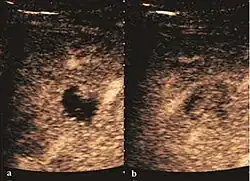

Fig. 11. Early hepatocellular carcinoma (2D, CFM). The 2D examination reveals a solid, hypoechoic nodule in IVth liver segment, without encapsulation. CFM shows a central vessel with ramifications to the periphery. The underlying liver is cirrhotic.

Fig. 12. Early hepatocellular carcinoma (2D, CFM). “Nodule in nodule” image: small hypoechoic early HCC inside monitored dysplastic nodule.

The suggestive appearance of early HCC on 2D ultrasound examination is that of hypoechoic nodule, with distinct pattern, developed on cirrhotic liver. Hypoechoic appearance is characteristic of moderate/poorly differentiated HCC, with low or absent fatty changes. Rarely, HCC may appear isoechoic, consist of a tumor type with a higher degree of differentiation and therefore with slower development. Another common aspect is "bright loop" or "nodule-in-nodule" appearance, hypoechoic nodules in a hyperechoic tumor.

Spectral Doppler characteristics of early HCC overlap those of the dysplastic nodule, as they are represented by the presence of portal venous signal type or arterial type with normal RI (well differentiated HCC) or increased RI (moderately or poorly differentiated HCC). The CFM exploration identifies a chaotic vessels pattern.

On CEUS examination, early HCC has an iso- or hypervascular appearance during the arterial phase followed by wash out during portal venous and late phase. There are studies showing that the wash out process is directly correlated with the size and features of neoplastic circulatory bed. Thus, highly differentiated HCC illustrates the phenomenon of late or even very late "wash out" while poorly differentiated HCC has an accelerated wash out at the end of arterial phase. It is therefore mandatory to analyze all these three phases of CEUS examination for a proper characterization of liver nodules. Tumor wash out at the end of the arterial phase allows the HCC diagnosis with a predictability of 89.5%. Some authors consider that early pronounced contrast enhancement of a nodule within 1–2 cm developed on a cirrhotic liver is sufficient for HCC diagnosis. These results prove that for a correct characterization of the lesions it is necessary to extend the examination time to 5 minutes or even longer.